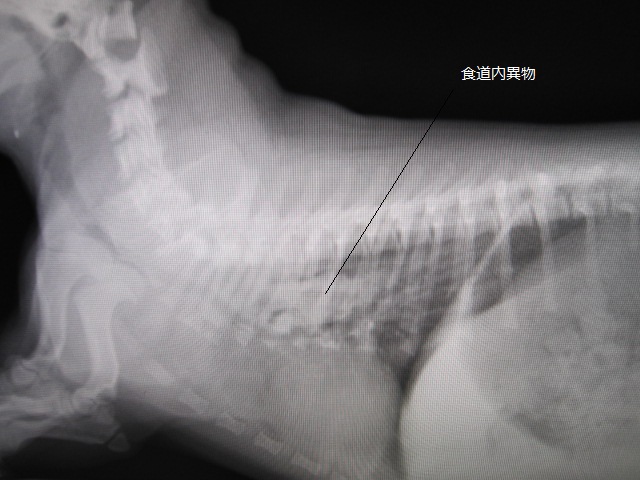

術前

術前のレントゲンです。

食道に異物がつまっています。

食道に砂ぎもがつまっています。